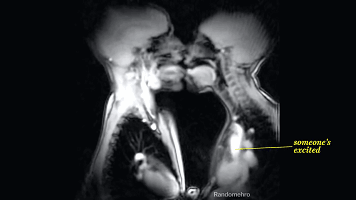

从下图可以看出两个人的舌头

都开始不老实了,接吻会加剧

兴奋,会使心跳速度进一步增加

呼吸也会更急促,全身的肌肉

开始出现不规则的收缩肌紧张